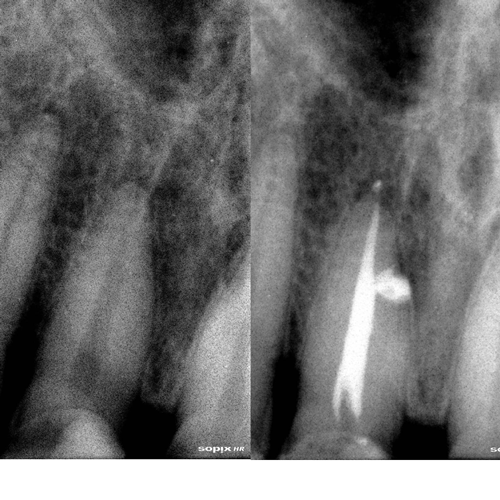

Nuestros procedimientos son realizados bajo magnificación microscópica